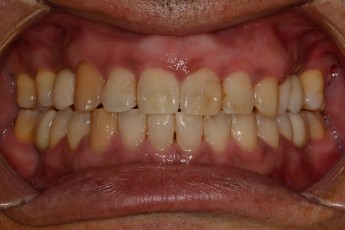

Before

After